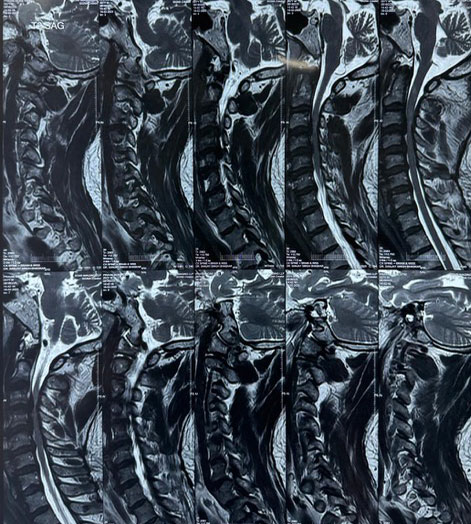

Dr. Ujwal Yeole is an experienced neurosurgeon specializes in treating a wide spectrum of neurological conditions including neuro-oncology, peripheral nerve disorders, vascular disorders, spinal pathologies, pediatric neurosurgery, neuro-trauma and skull base neuroendoscopic procedures.